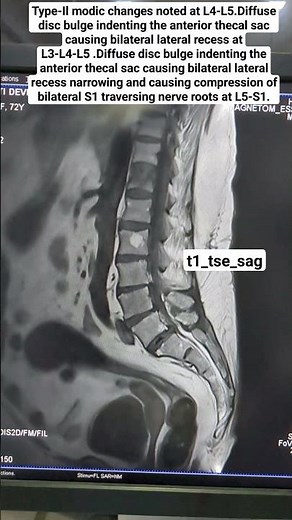

- Disc Bulging

L5-S1 - Disc

Protrusion L5-S1 MRI - L5-S1

L5-S1 - Spine MRI

L4-L5 Treatment - Herniated Disk